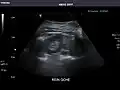

Renal ultrasonography

Ultrasound scan of a kidney (right side)

Ultrasonography of the kidneys is essential in the diagnosis and management of kidney-related diseases. The kidneys are easily examined, and most pathological changes in the kidneys are distinguishable with ultrasound.[7]

Kidneys: Right and left kidneys measure 11.5 cm and 12 cm in length respectively. No hydronephrosis. Small left lower pole kidney cyst.